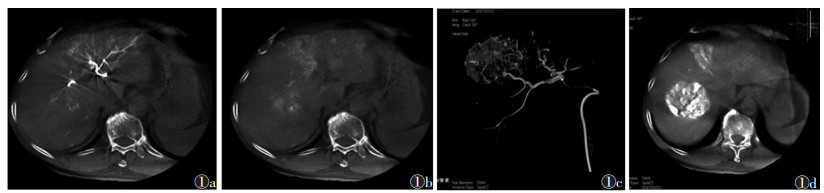

1.3 观察指标分析CBCT双期扫描图像对应同一层面病灶显示的差异(图 1a); 观察动脉期数据是否可重建出三维血管图像, 分析三维血管图像是否显示肿瘤供血动脉, 从而指导超选择插管, 为后续栓塞提供依据; 记录MSCT、CBCT双期扫描及碘化油CT发现的肿瘤病灶的大小及个数, 并以碘化油CT发现的肿瘤个数作为金标准, 对比MSCT与CBCT双期扫描的检查结果。

| 图 1 男,64岁,肝癌首次肝动脉化疗栓塞(TACE)治疗 图 1a,1b CBCT双期扫描均可见呈弥漫分布的肿瘤强化影像,动脉期可见由于对比剂充盈血管内而产生的伪影 图 1c 动脉期三维重建图像,可清晰区分肿瘤供血动脉 图 1d 碘化油栓塞后另一层面的CBCT平扫图像 |

2 结果100例中, 56例可重建出CBCT动脉期三维血管图像(图 1b), 并依据血管走行超选择插管到位顺利并成功栓塞。栓塞后CBCT平扫可评价栓塞效果(图 1c)。3例存在动脉期显示不明显而静脉期显示的病灶(图 2), 余46例动脉期与静脉期均可分辨病灶(图 3)。